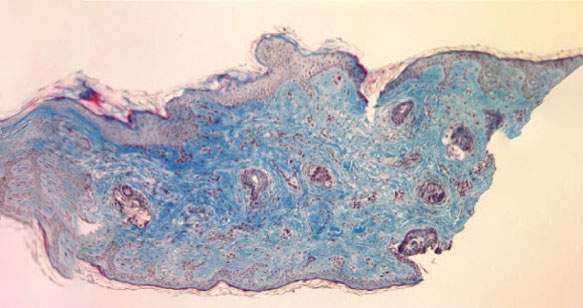

Aumento visibile della quantità di collagene (in blu) in 12 settimane di trattamento.

Biopsia prima del trattamento

12 settimane dopo il trattamento

Circa il 400% di aumento del collagene

Gli studi effettuati mostrano che Kleresca® Skin Rejuvenation induce un aumento di circa il 400% della produzione di collagene.